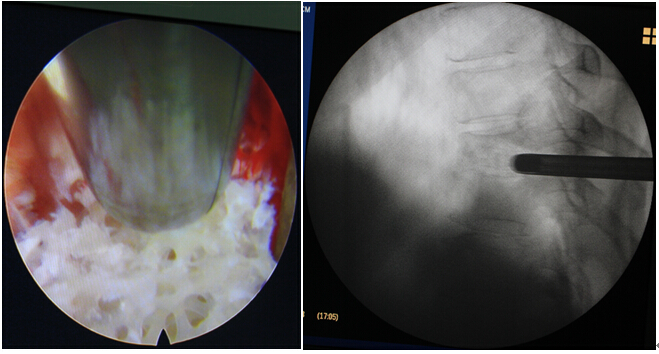

手术:1.经皮椎间孔镜下病灶清除、植骨。

体表定位                            成功置入工作通道

置入通道后透视

病灶清除后植入骨颗粒